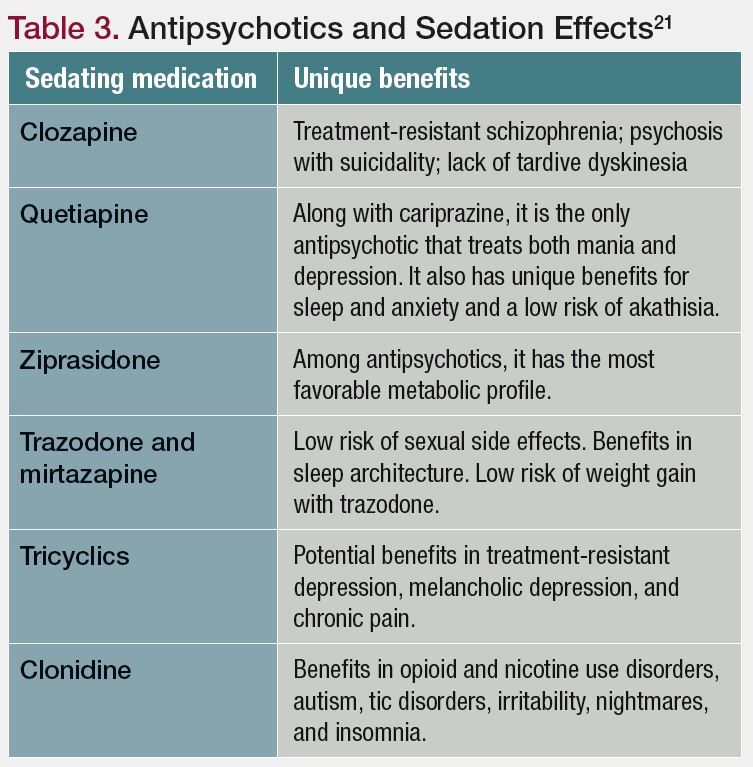

Sedation The Ups And Downs Of A Side Effect

Sedation The Ups And Downs Of A Side Effect

Sedation The Ups And Downs Of A Side Effect